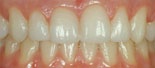

överbett före behandling överbett efter behandling

Före behandling av överbett Efter behandling av överbett